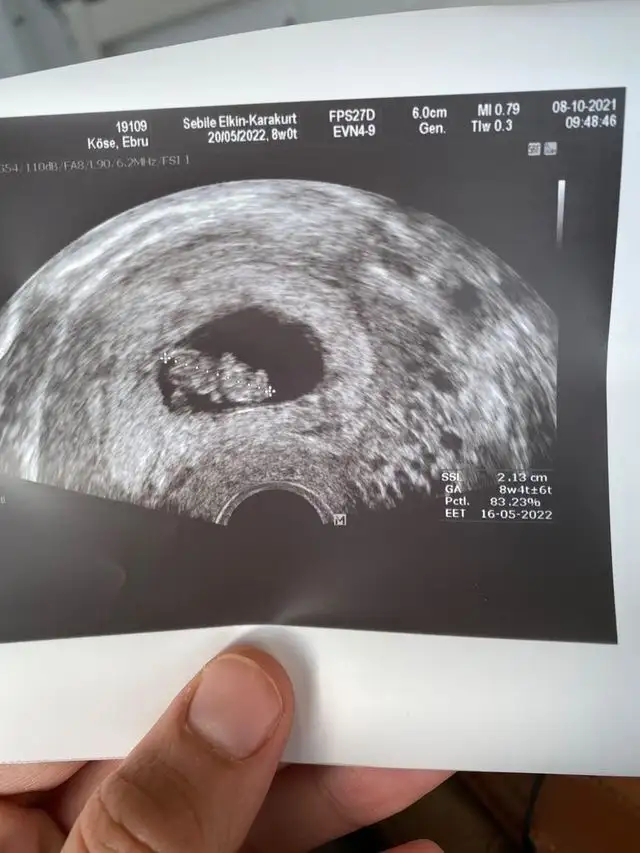

İlk usg yi atayım canimTam ortada

Buna göre karındansa kız. Vajinalse erkek.İlk usg yi atayım canim

Benim 3 kızım var canim bakalim bu inşallah erkek olur ilk usg yi de attım. Senin usg gibi ise oğluna hamilesin inşallah benim de oğlum olur.Cnim benim oglumun usg ayni bunun gibi ortadaydi ama kizlarinki tam soldaydi

Atar mısın canım elinde var mi bakabilir miyim bendeCnim benim oglumun usg ayni bunun gibi ortadaydi ama kizlarinki tam soldaydi

Canim benim ilk USG gibi sola doğru tutunmuş inşallah sağlıklı hayırlı oğlun olur kizlarimda bariz sağ tarafa yapisiktiİlk usg yi atayım canim